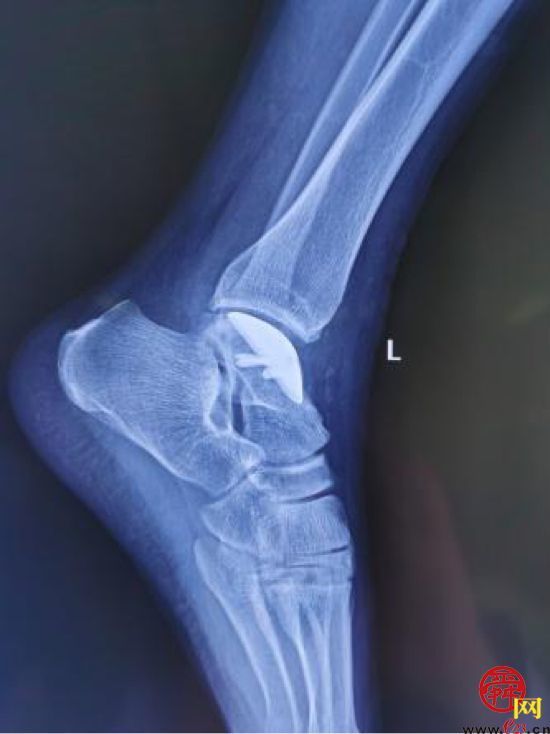

患者,男,28岁,左踝关节疼痛1年,加重3个月,影像学表现为左距骨内髁坏死、塌陷,面积约3*2cm大小。距骨坏死的治疗,对直径在2cm以内的距骨坏死,可以采用自体股骨髁骨软骨移植、自体带骨膜髂骨移植等方法,但对于直径超过2cm的距骨坏死,尤其是年轻患者,一直是治疗的难点。搜索国内外文献,对于超过2cm距骨坏死,一般采用踝关节融合、踝关节置换、同种异体距骨移植、全距骨置换等方法。但上述方法均有弊端:采用关节融合,患者丧失踝关节功能;踝关节置换、全距骨置换对于年轻、距骨单髁坏死患者,创伤大,且需要多次的返修手术;国外有采用同种异体新鲜距骨移植的报道,但目前国内还没有相关的骨组织工程库。经手术团队术前充分讨论,认为3D打印技术因其个性化的设计已经越来越多地应用于临床,决定对患者行3D打印距骨部分置换手术。

(术前患者的影像情况)